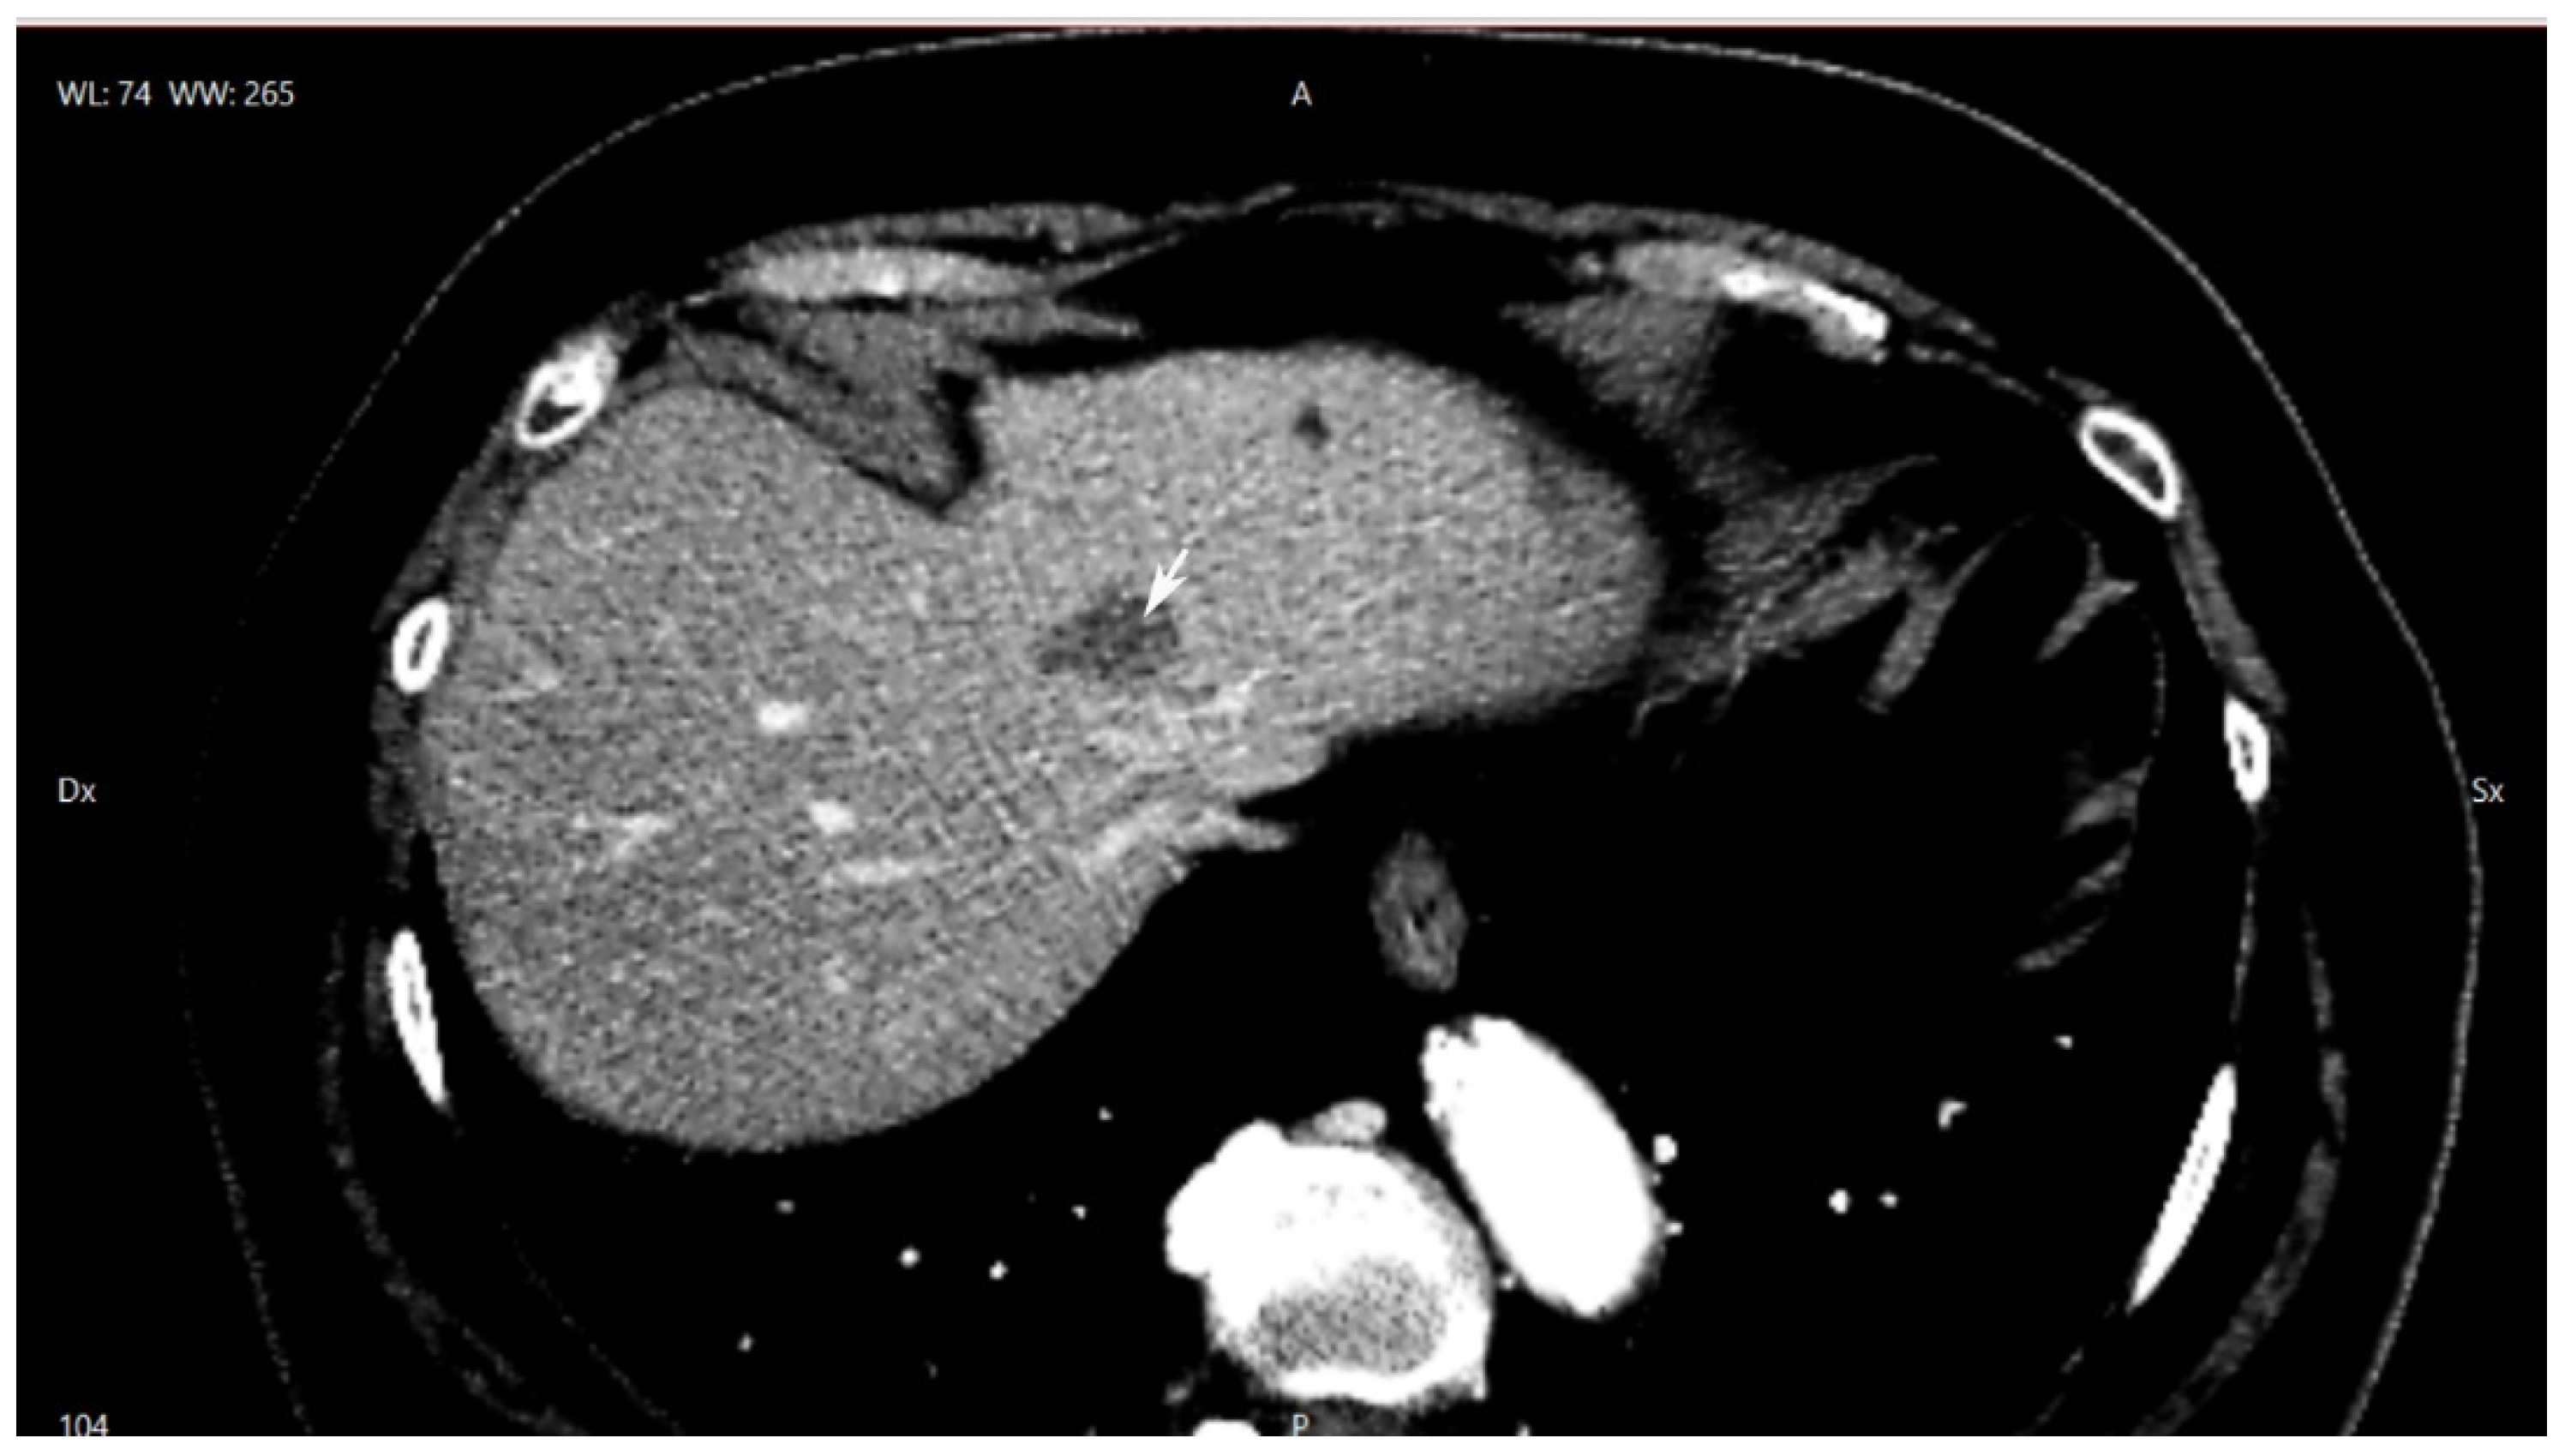

Laparoscopic Resection of Synchronous Liver Metastasis Involving the Left Hepatic Vein and the Common Trunk Bifurcation: A Strategy of Parenchyma-Sparing Resection with Left Sectionectomy and 4a Subsegmentectomy by Arantius Approach

2. Case Presentation